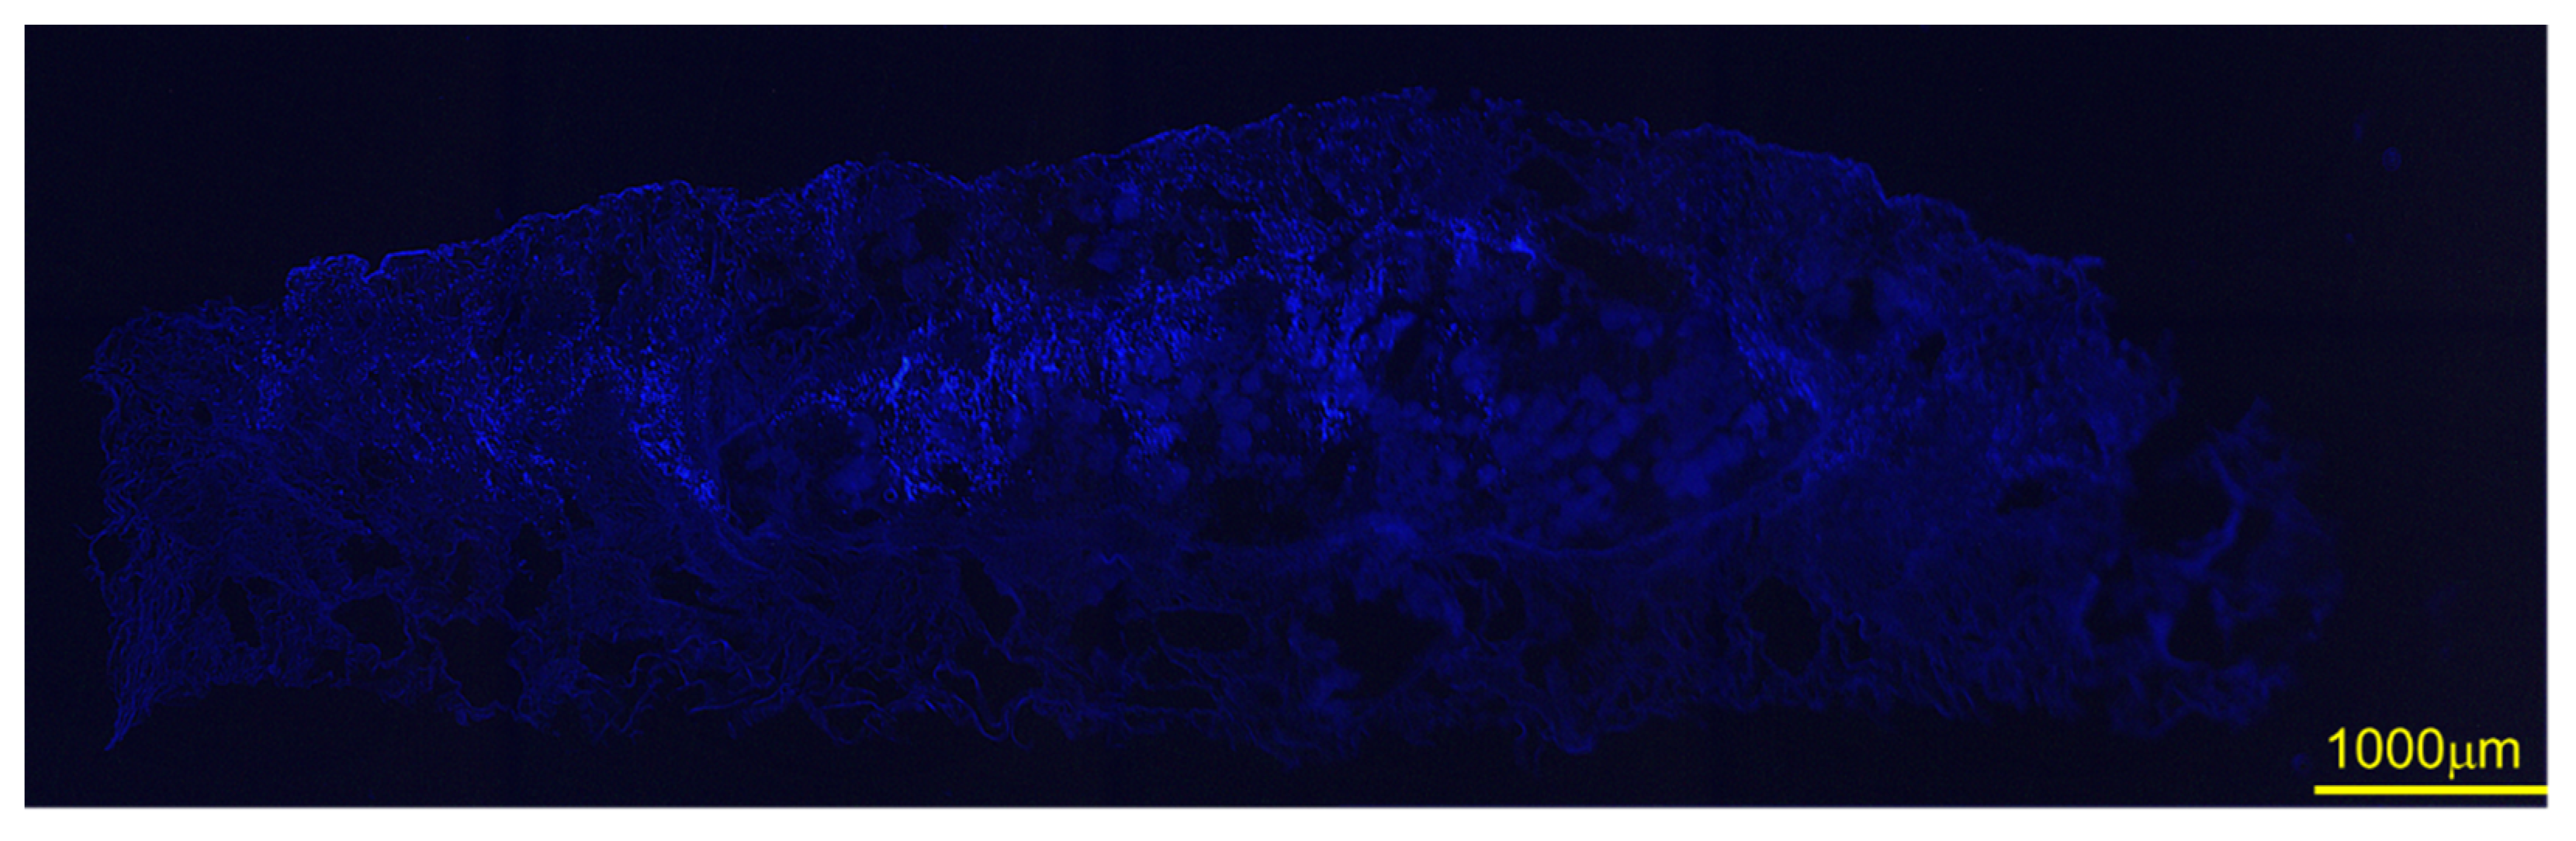

3.7. SEM after DFAT Seeding and DAPI Staining

3.8. Bone Morphometric Analysis